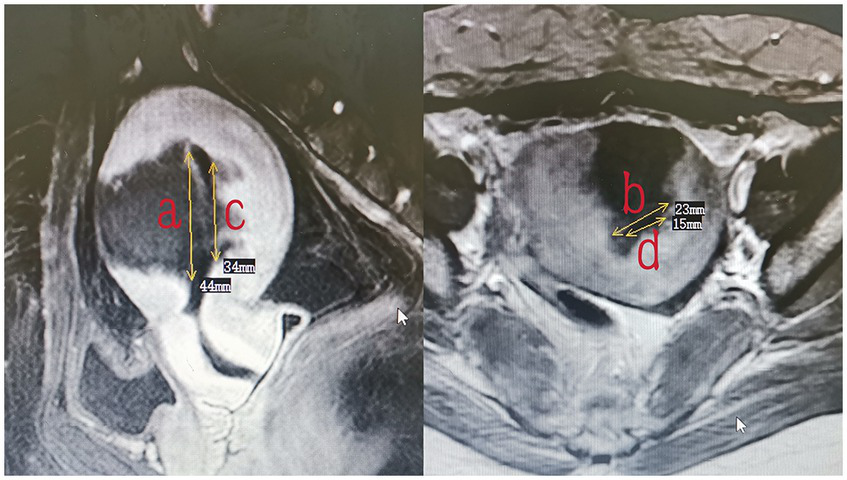

The endometrium of the uterine cavity is an inverted triangle, and the uterine cavity has two sides. The area of the endometrium was measured using the following equation: area = 0.5 × a × b (a and b are the longitudinal and transverse dimension, respectively) × 2. The measurements of the area of the intact endometrium and ablated endometrium were based on preoperative (Figure 3) and postoperative MRI findings (Figure 4), respectively. The ablation rate was defined as the area of frustrated endometrium divided by the area of endometrium. Ablation rate = (area of frustrated endometrium/area of endometrium) × 100%. Successful treatment with HIFU was determined as the occurrence of a destruction rate of ≥25%.

Figure 3

The measurement of the area of endometrium (area = 0.5 × a × b × 2).

Figure 4

The measurement of the area of frustrated endometrium (area = 0.5 × a × b + 0.5 × c × d).